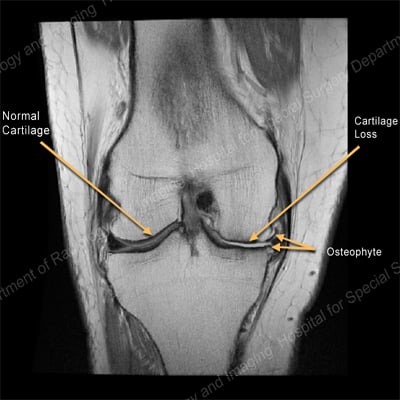

Magnetic resonance imaging (MRI)

Magnetic resonance imaging is very sensitive imaging that can reveal subtle changes in bony and soft tissues. An MRI can show reactive bone edema (fluid build-up in the bone marrow), inflammation of soft tissues, as well as degenerated cartilage and damage to other soft tissues associated with OA. HSS uses a protocol of MRI pulse sequences with high sensitivity and accuracy to identify early evidence of cartilage degeneration. When evidence of cartilage generation is detected early, appropriate treatment can begin to minimize further degeneration, possibly postponing or eliminating the need for surgery.

MRI of the knee showing normal cartilage on one side and cartilage loss and an osteophyte on the other.